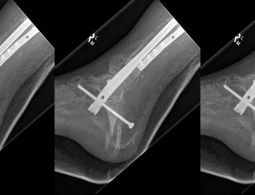

Напечатанную на 3D-принтере берцовую кость имплантировали пациенту

Экспериментальная операция помогла 27-летнему австралийцу сохранить ногу. Ройбен Лихтер страдал серьёзной формой остеомиелита и ему грозила ампутация ноги, но врачи предложили ему попробовать новый способ, ранее тестировавшийся только на животных. В результате хирурги имплантировали ему в ногу ...